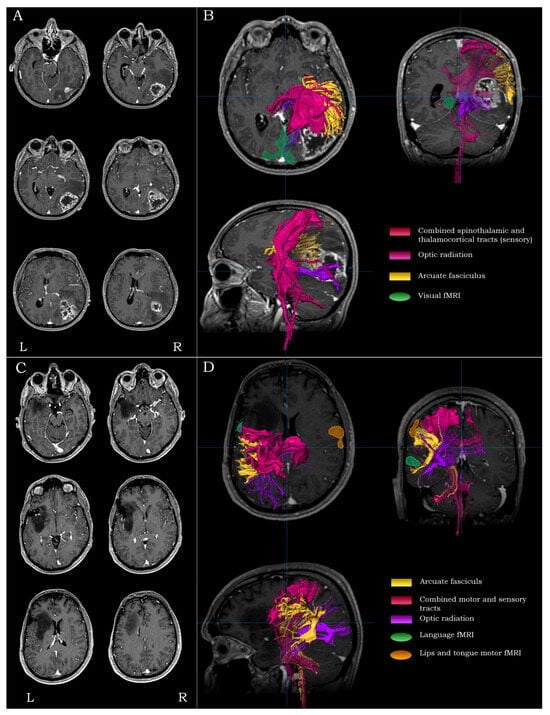

For lesions residing in the temporo-occipital regions (Brodmann areas 19, 30 and 37), the main surgical concerns were the proximity to primary visual and receptive language areas, the proximity to the primary somatosensory cortex and the integrity of the optic radiation. For such lesions, the mapping process included visual fMRI (and language fMRI depending on the extent of the lesion), as well as DTI-tractography of the arcuate fasciculus, the combined spino-thalamic/thalamo-cortical tracts and the optic radiation (Figure 4A,B).

Figure 4.

Examples highlighting the strategy and rationale of functional and structural peri-lesional coverage. Anatomical localization and morphological depiction (A), along with fMRI and DTI-tractography mapping (B), on post-G Gadolinium T1-weighted images for a posterior quadrant tumor. Anatomical localization and morphological depiction (C), along with fMRI and DTI-tractography mapping (D), on post-G Gadolinium T1-weighted images for a multi-lobar (frontal/insular/temporal) tumor.